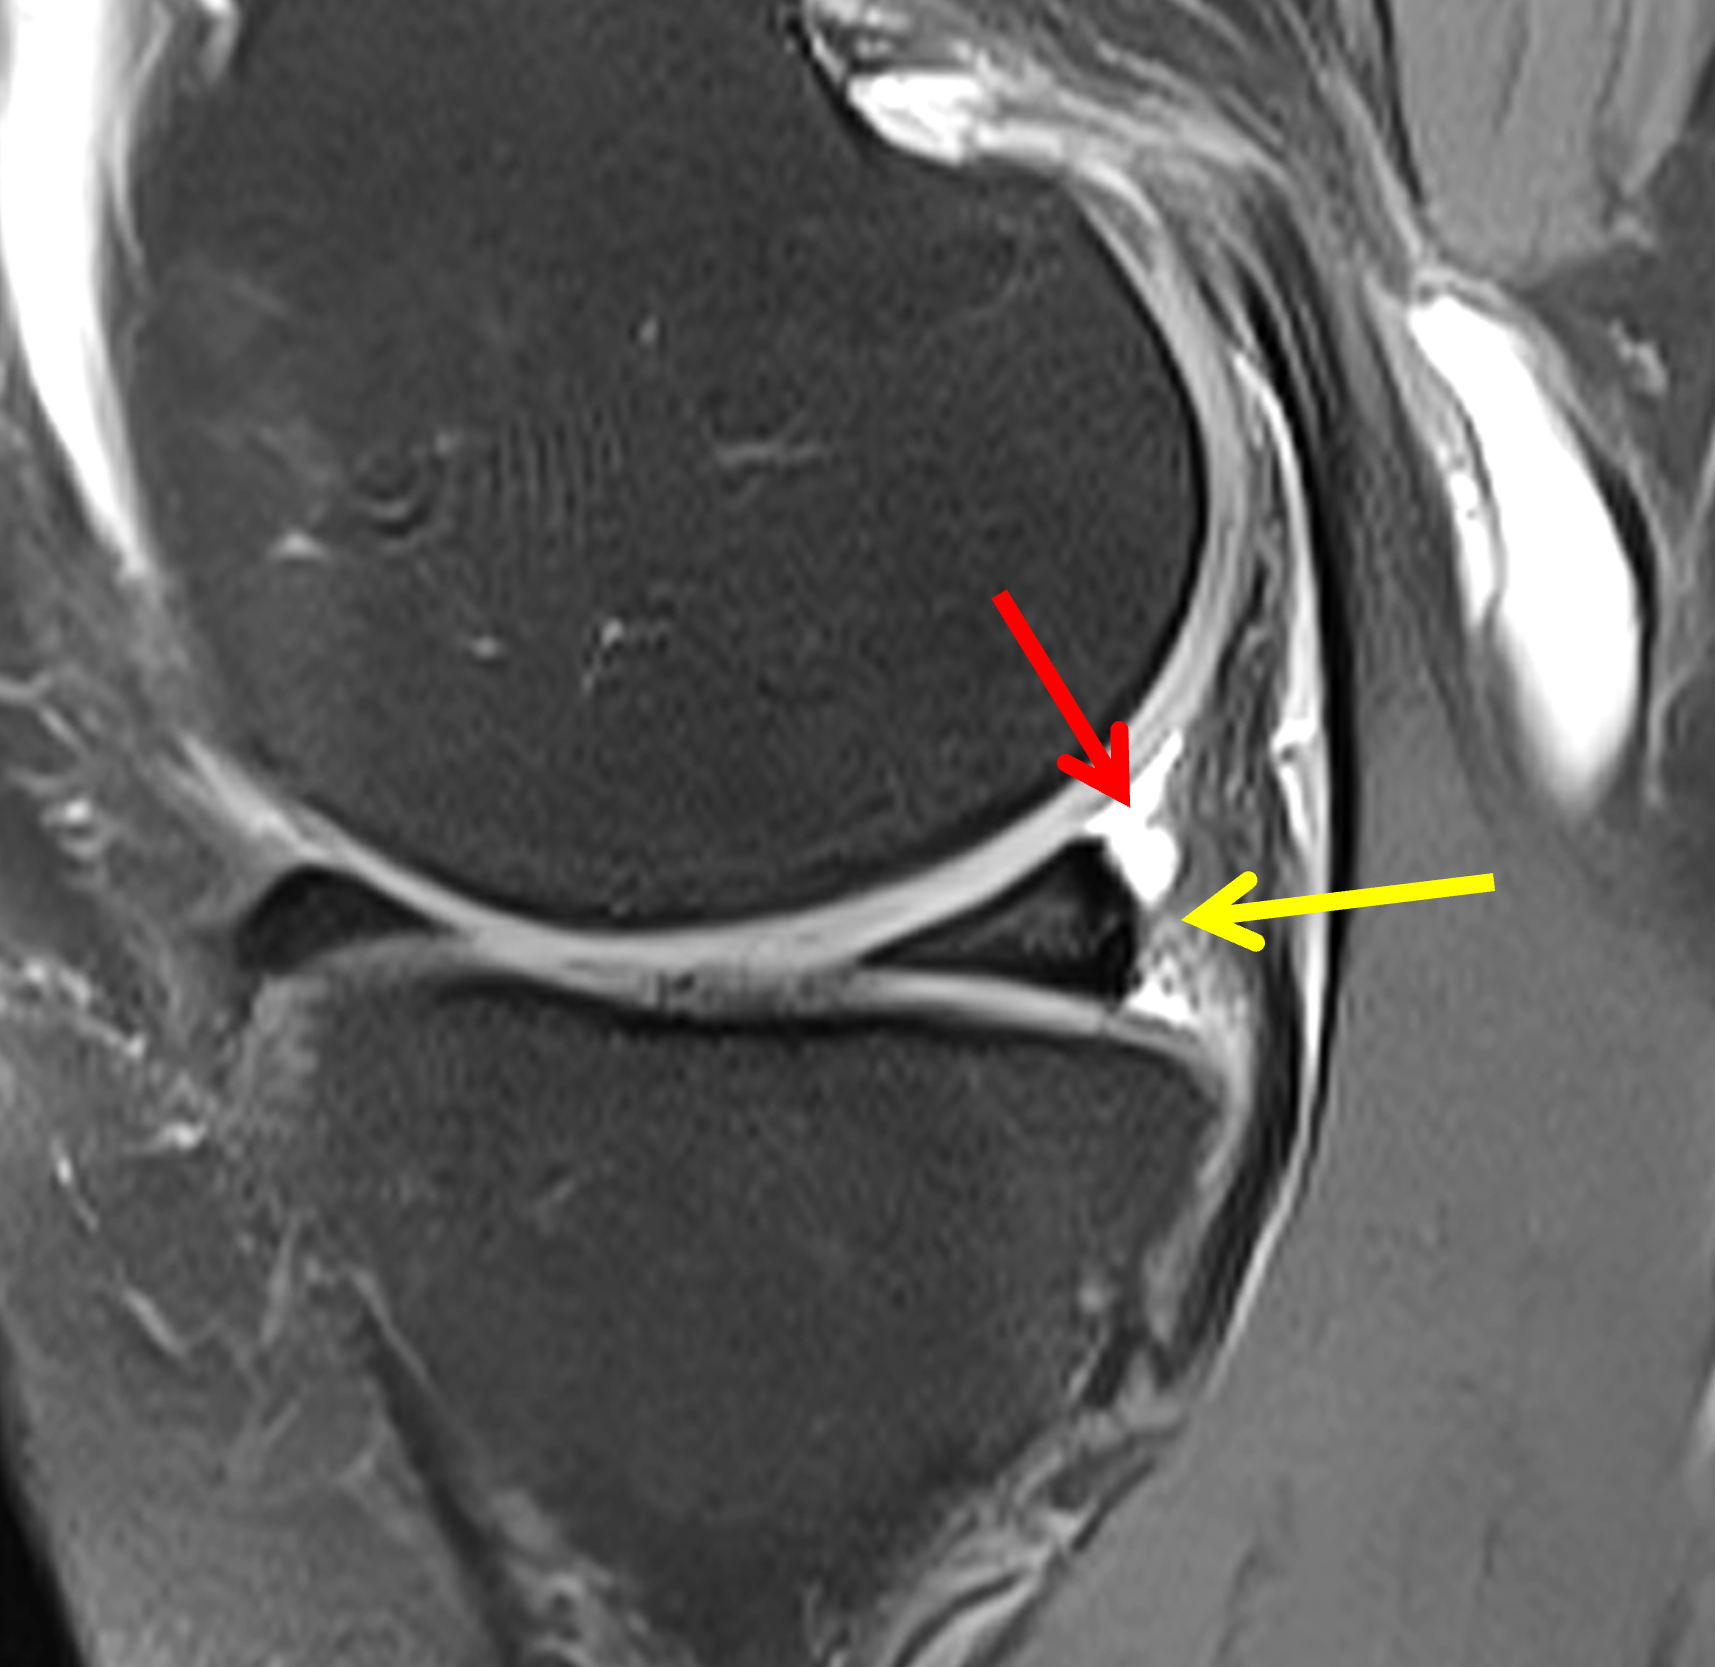

A 19-year-old collegiate baseball player sustained a twisting injury to the knee 3 weeks earlier. Sagittal (1A) proton density-weighted fat-suppressed image through the intercondylar notch, (1B and 1C) proton density-weighted images through the medial compartment, and (1D) fat-suppressed proton density image through the medial compartment are provided. What are the findings? What is your diagnosis?

Figure 2: (2A) Sagittal image through the intercondylar notch shows a complete tear of the anterior cruciate ligament (arrowheads). (2B and 2C) Near the posterior meniscocapsular junction of the medial meniscus, there is disruption of the posterior meniscotibial ligament (red arrow) and irregularity of the posterior meniscocapsular ligament (yellow arrow). (2D) On the fluid-sensitive sequence, linear high signal intensity is interposed between the ligaments and the posterior horn of the medial meniscus (arrowheads).

Anterior cruciate ligament tear with a medial meniscal ramp lesion.